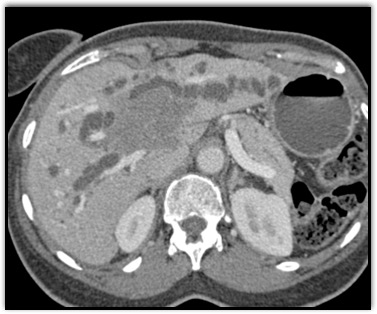

The least likely diagnosis in this case is?

cholangiocarcinoma

lymphoma

carcinoid tumor

hepatoma